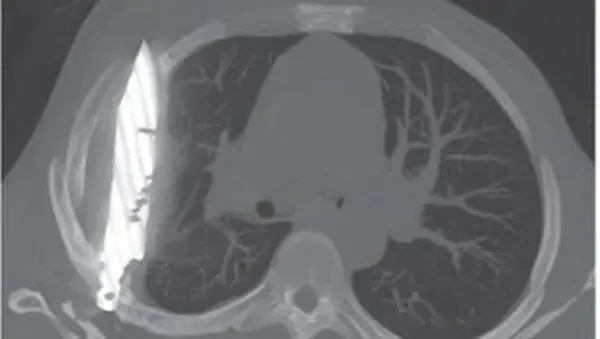

Penampakan pisau menancap di dada seorang pasien pria. Foto: Journal of Surgical Case Reports |

"Rontgen dada lateral awal menunjukkan adanya benda logam tersangkut di bagian tengah dada, dengan bayangan samar di sekitarnya yang mengindikasikan hematoma terlokalisasi kronis yang mengeluarkan cairan, atau fibrosis pascatrauma, kemungkinan besar akibat luka tusukan pisau pasien," tulis dokter dalam jurnal, dikutip dari News18, Selasa (19/8/2025).